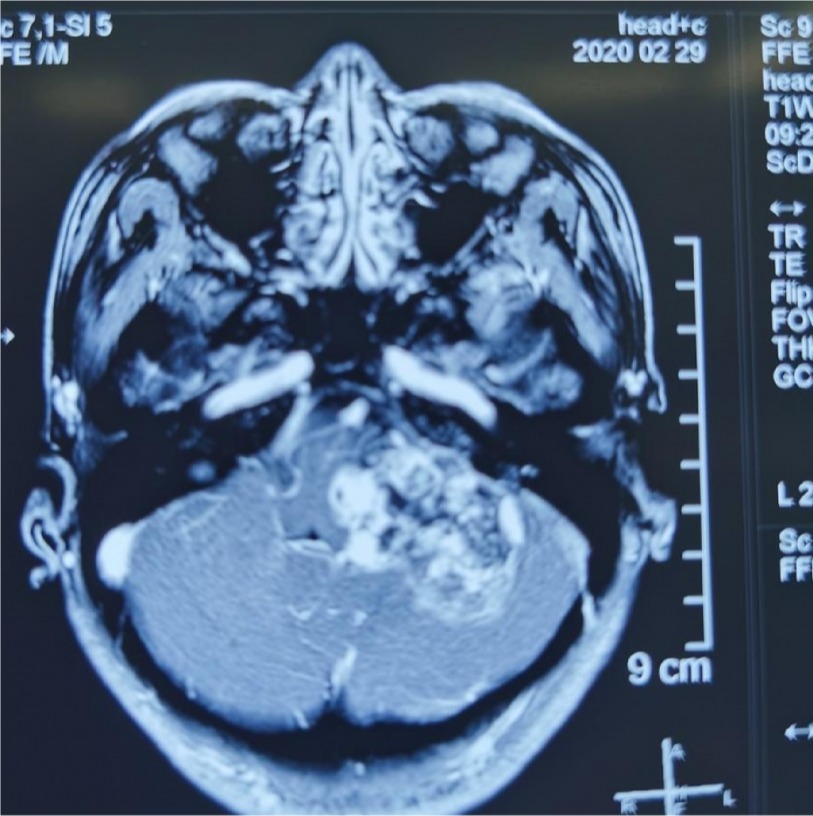

头颈部颈静脉孔神经鞘瘤

图片尺寸960x720